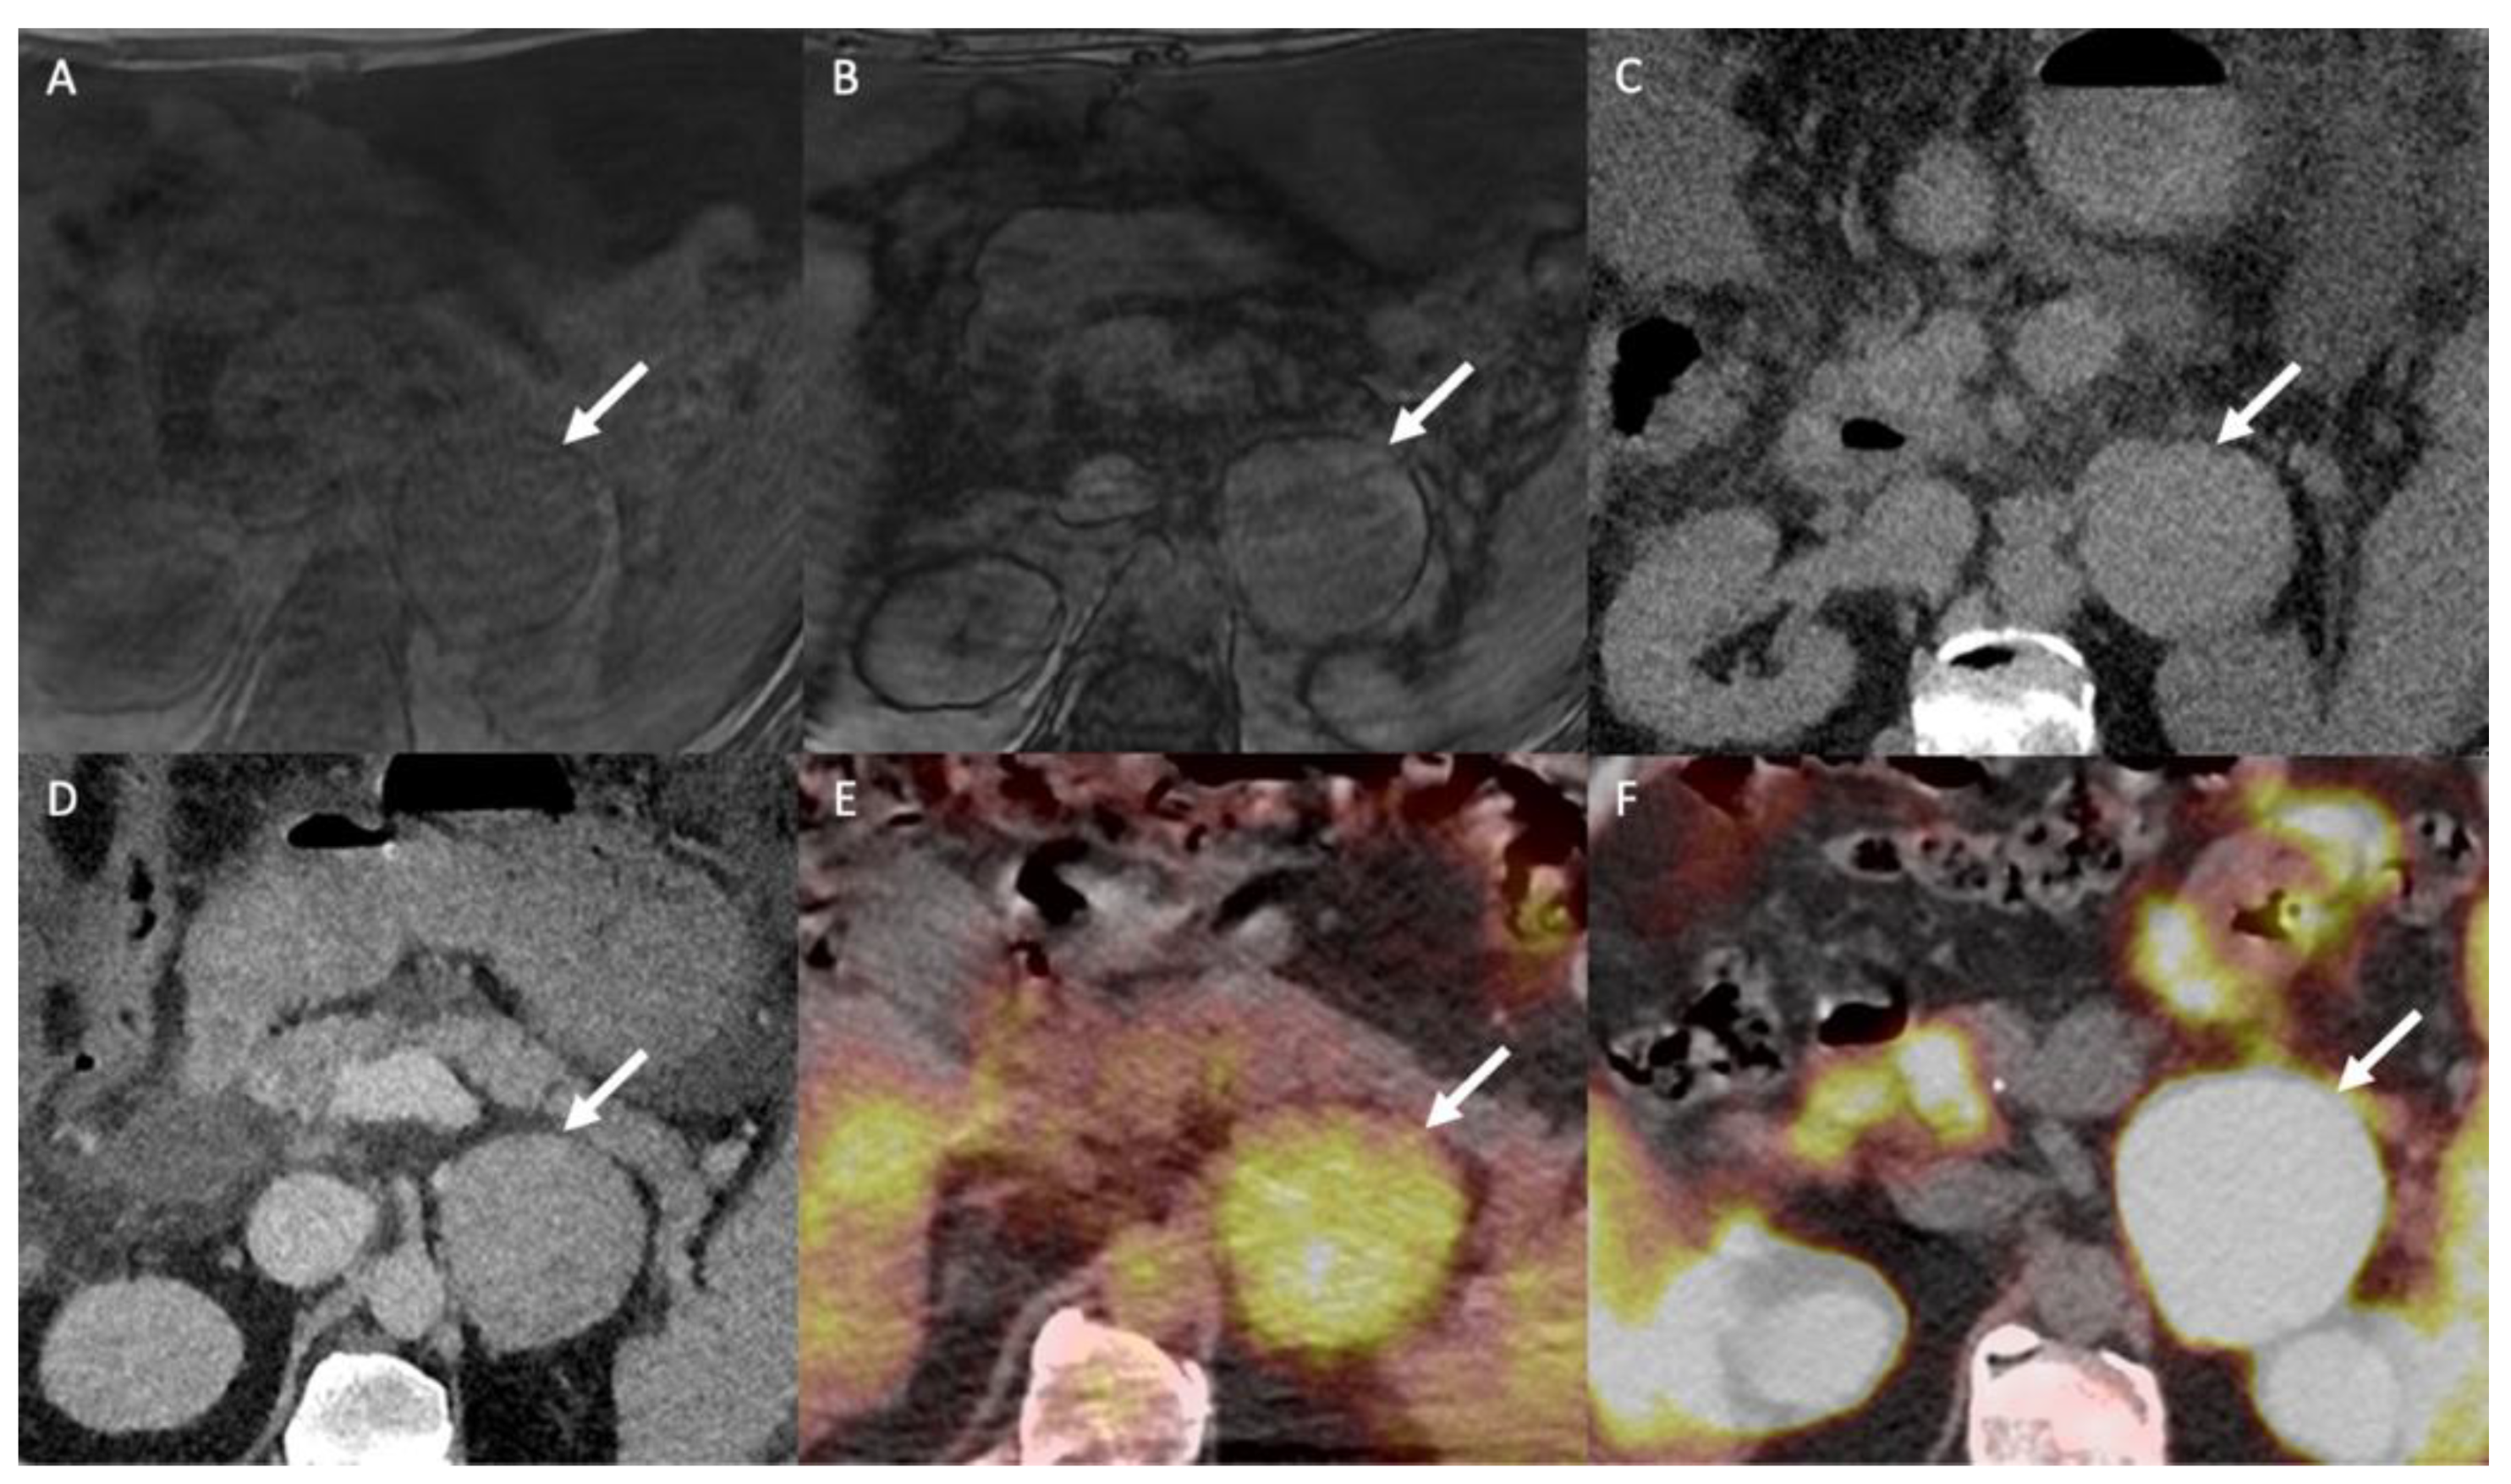

- Nagayama, Y.; Inoue, T.; Oda, S.; Tanoue, S.; Nakaura, T.; Ikeda, O.; Yamashita, Y. Adrenal Adenomas versus Metastases: Diagnostic Performance of Dual-Energy Spectral CT Virtual Noncontrast Imaging and Iodine Maps. Radiology 2020, 296, 324–332. [Google Scholar] [CrossRef]

- Lestra, T.; Mule, S.; Millet, I.; Carsin-Vu, A.; Taourel, P.; Hoeffel, C. Applications of dual energy computed tomography in abdominal imaging. Diagn. Interv. Imaging 2016, 97, 593–603. [Google Scholar] [CrossRef]

- Connolly, M.J.; McInnes, M.D.F.; El-Khodary, M.; McGrath, T.A.; Schieda, N. Diagnostic accuracy of virtual non-contrast enhanced dual-energy CT for diagnosis of adrenal adenoma: A systematic review and meta-analysis. Eur. Radiol. 2017, 27, 4324–4335. [Google Scholar] [CrossRef] [PubMed]

- Greffier, J.; Frandon, J. Spectral photon-counting CT system: Toward improved image quality performance in conventional and spectral CT imaging. Diagn. Interv. Imaging 2021, 102, 271–272. [Google Scholar] [CrossRef] [PubMed]